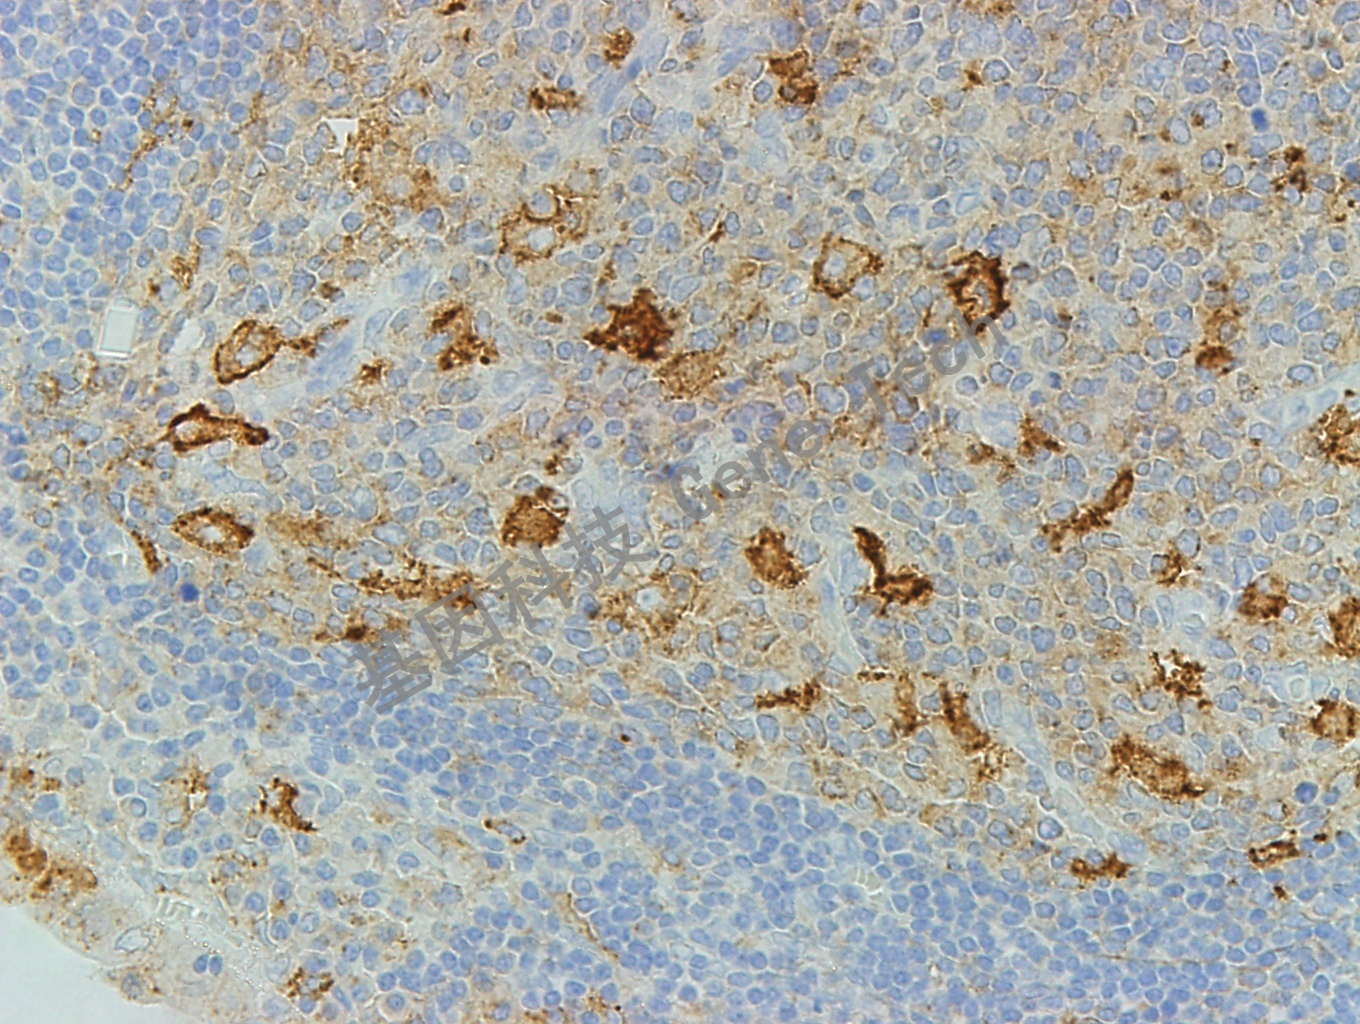

扁桃体石蜡切片,用 CD71(GT2143)染色,细胞膜/细胞浆阳性,DAB显色。(10×)

扁桃体石蜡切片,用 CD71(GT2143)染色,细胞膜/细胞浆阳性,DAB显色。(40×)